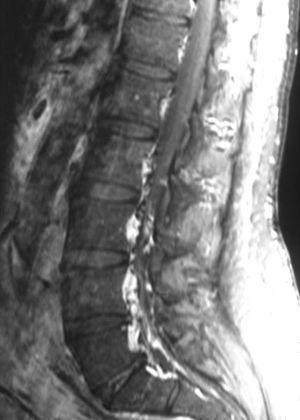

Fig. 3. Resonancia magnética tras contraste intravenoso: (A) sagital línea media y (B) axial. Se aprecia masa retroperitoneal (asterisco) y dilatación secundaria de las venas radiculares. Nótese la deformidad del saco tecal provocada por lipomatosis epidural (flechas).